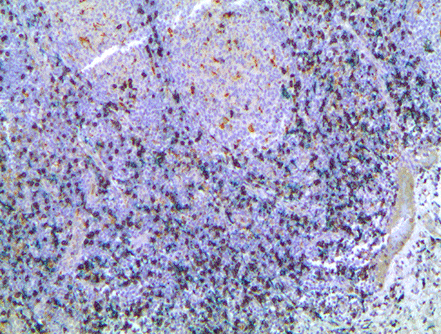

對福爾馬林固定石蠟包埋的人扁桃體進行多重 IHC 染色,該抗體用 HIGHDEF 黑色 IHC 色原 (HRP) 標記的 CD8 抗體染色(ADI-950-171)、用 HIGHDEF 黃色 IHC 色原 (HRP) 標記的 CD68 抗體(ADI-950-170)、用 HIGHDEF??? 綠色 AP 色原/底物標記的 CD163 抗體(參考文獻 ENZ-ACC130)和蘇木精復(fù)染。圖片由法國維勒瑞夫古斯塔夫·魯西癌癥校區(qū) Plateforme de Pathologie Expérimentale et Translationnelle - PETRA、Unité AMMICa、Gustave Roussy 癌癥校區(qū)提供。

技術(shù)信息/產(chǎn)品說明: HIGHDEF? 黑色 IHC 色原 (HRP) 是一種底物色原系統(tǒng),設(shè)計用于使用辣根過氧化物酶時的免疫組織化學 (IHC) 或 ISH。HIGHDEF 黑色 IHC 色原 (HRP) 產(chǎn)生鮮明對比的烏木黑色,很容易與其他污漬區(qū)分開來。